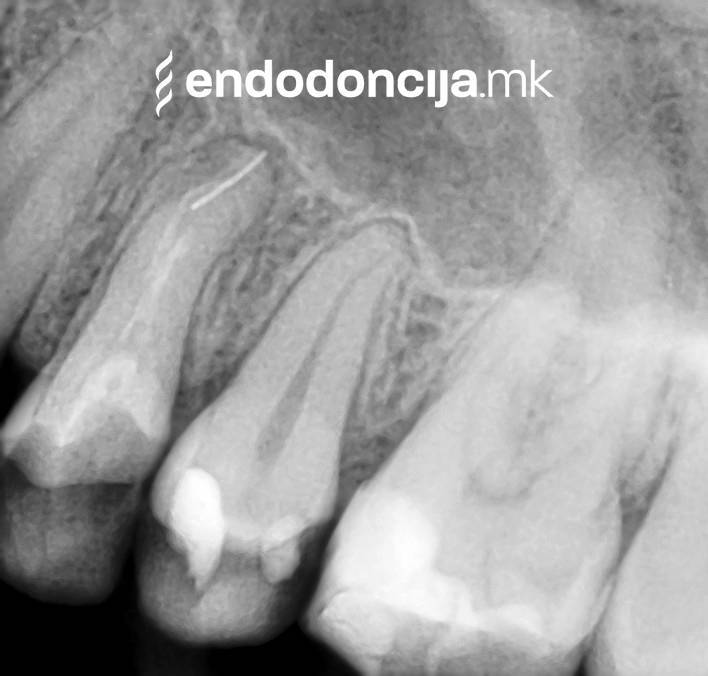

Κατά τη διάρκεια προηγούμενων θεραπειών, το δόντι μπορεί όχι μόνο να έχει αποδυναμωθεί από τη μηχανική επεξεργασία του ριζικού σωλήνα αλλά και από τη στερέωση και την αγκύρωση ενός ρίζα. Όταν αναθεωρείται η επεξεργασία ενός ριζικού καναλιού, αυτοί οι πείροι πρέπει να αφαιρούνται όσο το δυνατόν πιο προσεκτικά για να διατηρούν σημαντική ουσία των δοντιών.